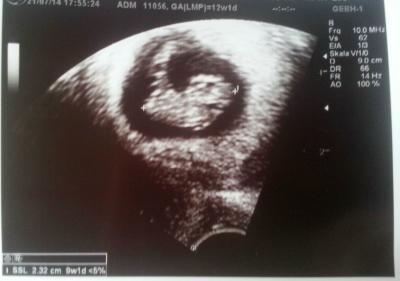

Hallo Ihr Lieben, ich war ja heute auch beim FA und trotz Blutungen vorletzte Woche ist alles super. Der kleine Wurm hat sich super weiterentwickelt und gewachsen ist er auch. Bin aber weiter als anfangs gedacht und mein ET ist jetzt der 21.-22. Februar 2015. Wünsche euch allen trotzdem noch eine schöne Kugelzeit und werde ab und zu noch mal hier rein schauen. P.S. noch ein Bild von meinem kleinen Krümel

Bild zu Leider doch keine März-Mami.... - Forum für März - Mamis